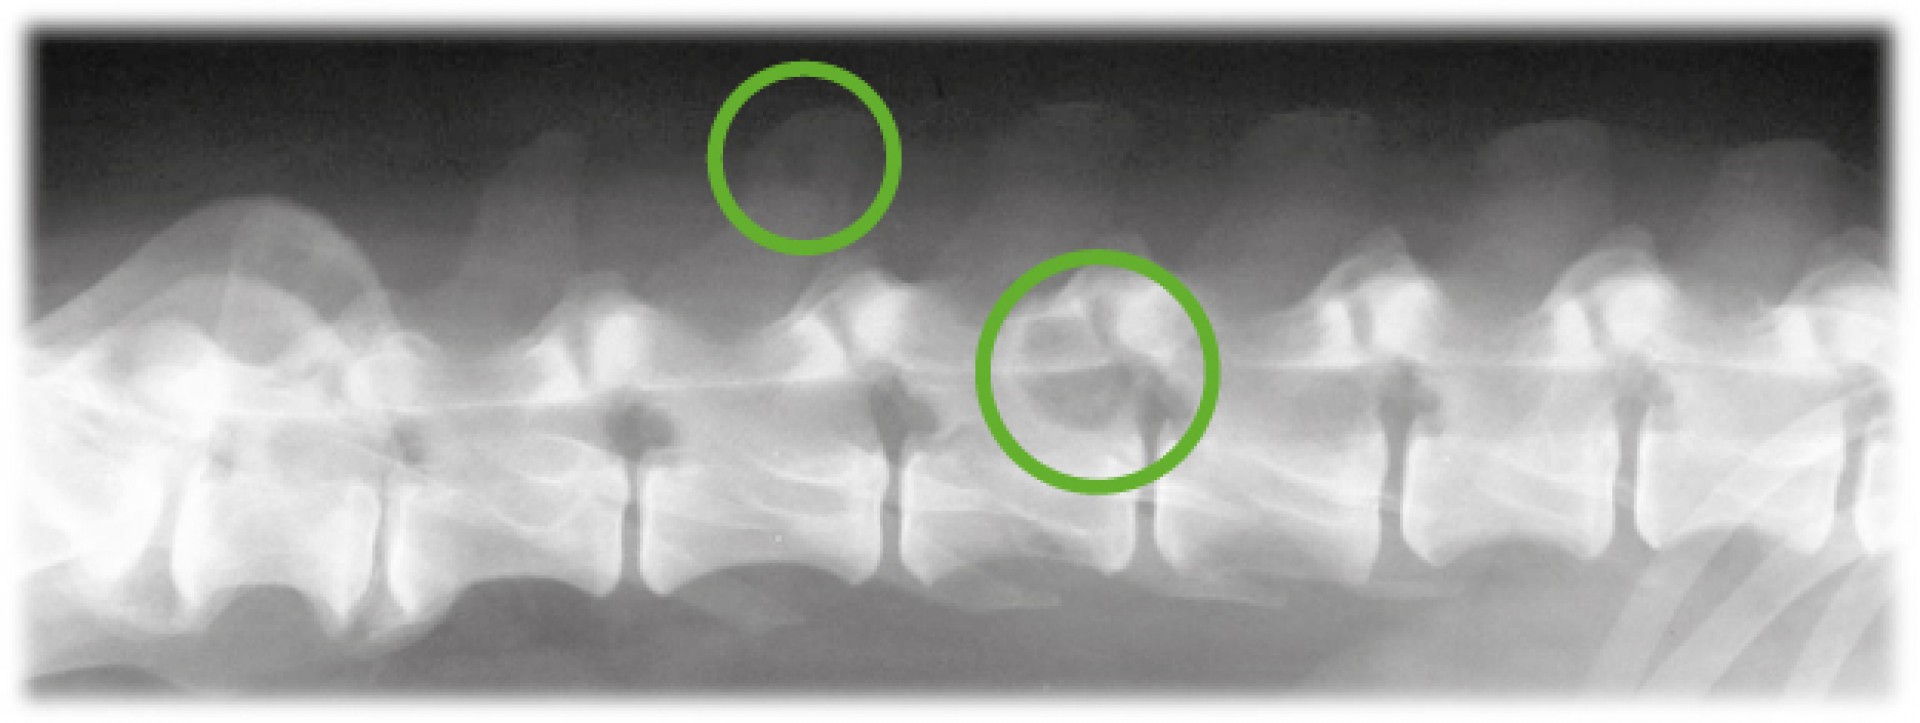

Míg az utóbbi esetben az elsődleges daganat eltávolítását, szövettani vizsgálatát követően az áttétes daganatok kemoterápiás/ sugárterápiás gyógykezelési lehetősége merül fel elsődlegesen, addig a primer gerincdaganatok kialakulása esetén annak pontos lokalizációját, a gerincoszlop alkotóelemeinek érintettségének maghatározását követően a daganat műtéti eltávolítására is sor kerülhet.A klinikai tünetek kialakulása sokféle lehet, szinte minden esetben egy folyamatosan rosszabbodó, idegrendszeri tünetek súlyosbodásával járó, gyakran azonos oldali mellső és hátsó végtagot érintő neurológiai kiesést tapasztalunk. A klinikai tünetek alapján azonban a gerinc daganatos megbetegedései nem különíthetőek el a hasonló kórlefolyású degeneratív megbetegedésektől (pl.: porckorongsérv). Így a diagnózis pontos felállításához kiegészítő vizsgálatokra mindenképpen szükség van. Ezek közé tartozik a natív röntgenvizsgálat, de mivel a gerincvelő környéki, a csontvázat nem érintő daganatok többnyire nem adnak röntgenárnyékot, ezért az egyszerű röntgen vizsgálaton túl egyéb képalkotó eljárásokra, kiegészítő vizsgálatokra is szükség lehet.